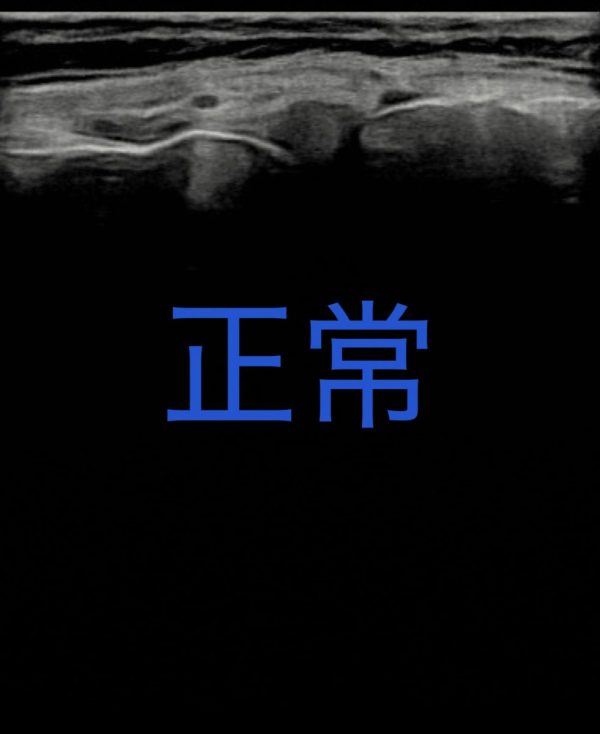

| グレード | エコー、レントゲンの画像所見 |

| 0(正常) | 正常 |

患者の年代、圧痛箇所、関節水腫、

動作開始時痛から、変形性膝関節症。

エコー画像によりグレード3と推測する。